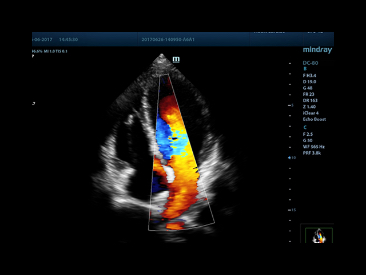

The best patient care is your ultimate goal. To achieve this requires confident diagnosis even with daily increases in patient throughput. Built on the foundation of MindrayвАЩs continuous customer insights into clinical needs and the inheritance from premium technology, the DC-80 with X-Insight is designed to help you manage your daily output with high efficiency, no matter what type patients and clinical challenges you will face.

eXceptional intelligence

Intelligence throughout entire workflow